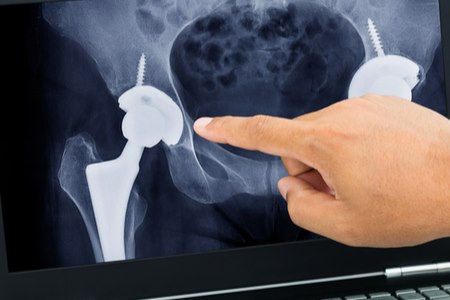

יש חשיבות עליונה להתאים את הניתוח למטופל, באופן אישי. צילום: שאטרסטוק

כפי שניתן להבין, לכל אחת מהגישות שהוזכרו לעיל, יש יתרונות וחסרונות מסוימים; לא כל גישה מתאימה לכל המועמדים. אי לכך, יש חשיבות עליונה להתאים את הניתוח למטופל - באופן אישי. כאשר מתאימים את הניתוח הרלוונטי למטופל, יש לקחת בחשבון את הנתונים האישיים שלו, את מצב המפרק, את רמת המיומנות של המנתח בביצוע הניתוחים השונים ועוד.